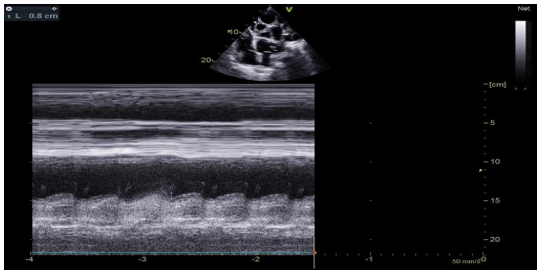

The transthoracic echocardiographic examination revealed (Figures 8 – 18):

- A lobulatedcystic image exerting severe compression on both the right and left cardiac chambers, resulting in hemodynamic disturbance and considerable fluctuation in respiratory flows (Figures 12 – 13,17).

- Left ventricule showed no sign of dilatation. Al though the assessment of contractile function was influeced by compressio from pulmonary hydatid cyst, it appears to maintain functionnality.

- Elevated left ventricular filling pressure were noted.

- The right ventricle exhibited no dilation (Figure 11) despite the presence of longitudinal systolicdys functio n (Figures 14).

- Grade II tricuspid insufficiency was identified, with an estimated systolic pulmonary arterial pressure of 47 mmHg (calculated as 37 + 10 mmHg), indicating the presence of pulmonary hypertension.

- The inferior vena cavademonstrated no dilation (Figure 18) and wasnoted to be non-compliant (Figure 16).

- No pericardial effusion was present.